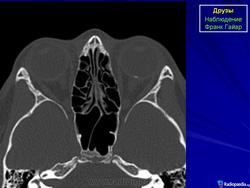

При КТ-исследовании изредка попадаются больные с наличием у них в области диска зрительного нерва плотных включений, которые могут быть приняты за инородные тела. Это так называемые друзы. Друзы диска зрительного нерва – довольно редкое заболевание, характеризующееся гроздевидными округлыми возвышениями над диском нерва, состоящими из гиалина. Иногда в них откладывается известь. Считают, что друзы имеют наследственный характер.

КТ-семиотика

При КТ друзы отличаются локализацией – только в диске зрительного нерва, небольших размеров (не более одного миллиметра) и правильной округлой формы. Друзы совершенно однородны, не дают артефактов и имеют определенную плотность (150-200 НU).